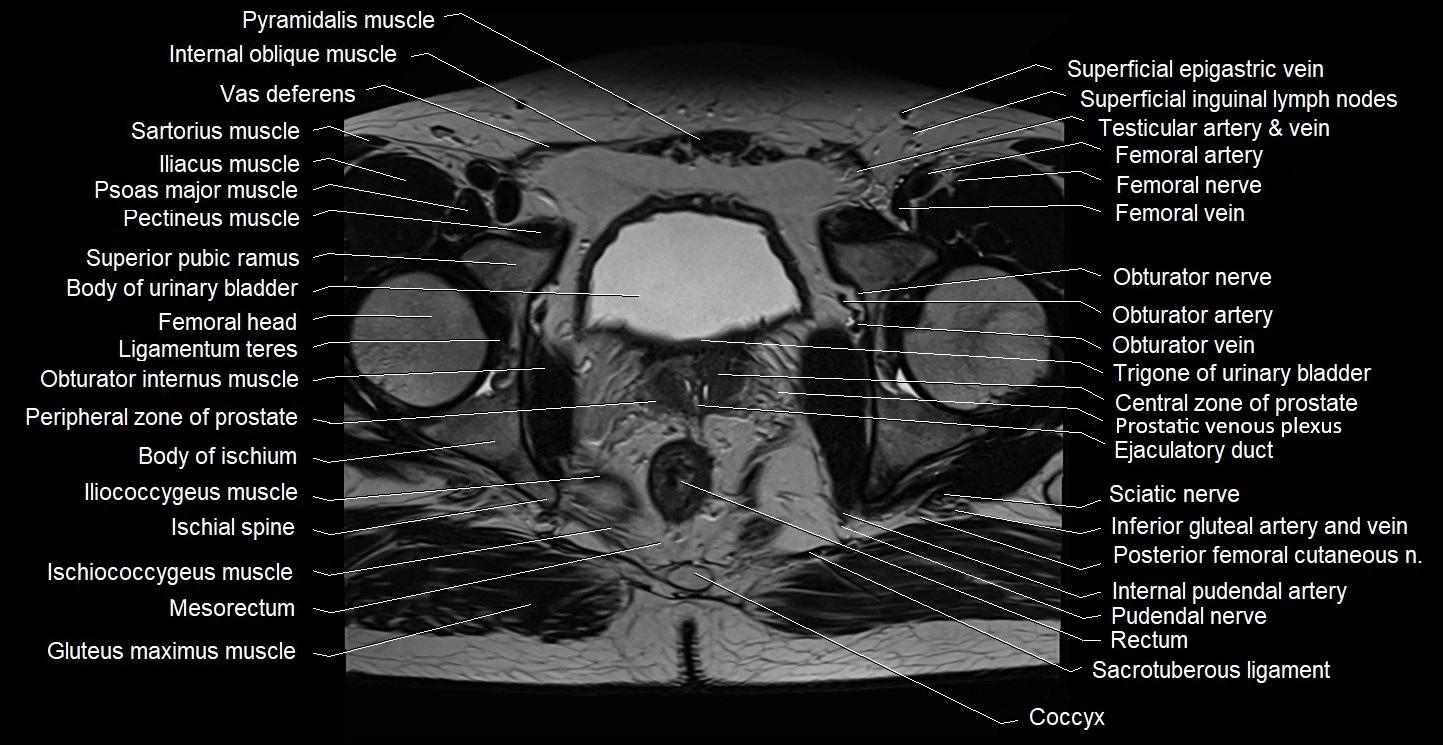

- Body of urinary bladder

- Central zone of prostate

- Ejaculatory duct

- Iliococcygeus muscle

- Internal oblique muscle

- Ischial spine

- Ischiococcygeus muscle

- Ligamentum teres (ligament of the head of femur)

- Mesorectum

- Obturator internus muscle

- Pectineus muscle

- Peripheral zone of prostate

- Posterior femoral cutaneous nerve

- Psoas major muscle

- Pudendal nerve

- Sartorius muscle

- Sciatic nerve

- Trigone of urinary bladder